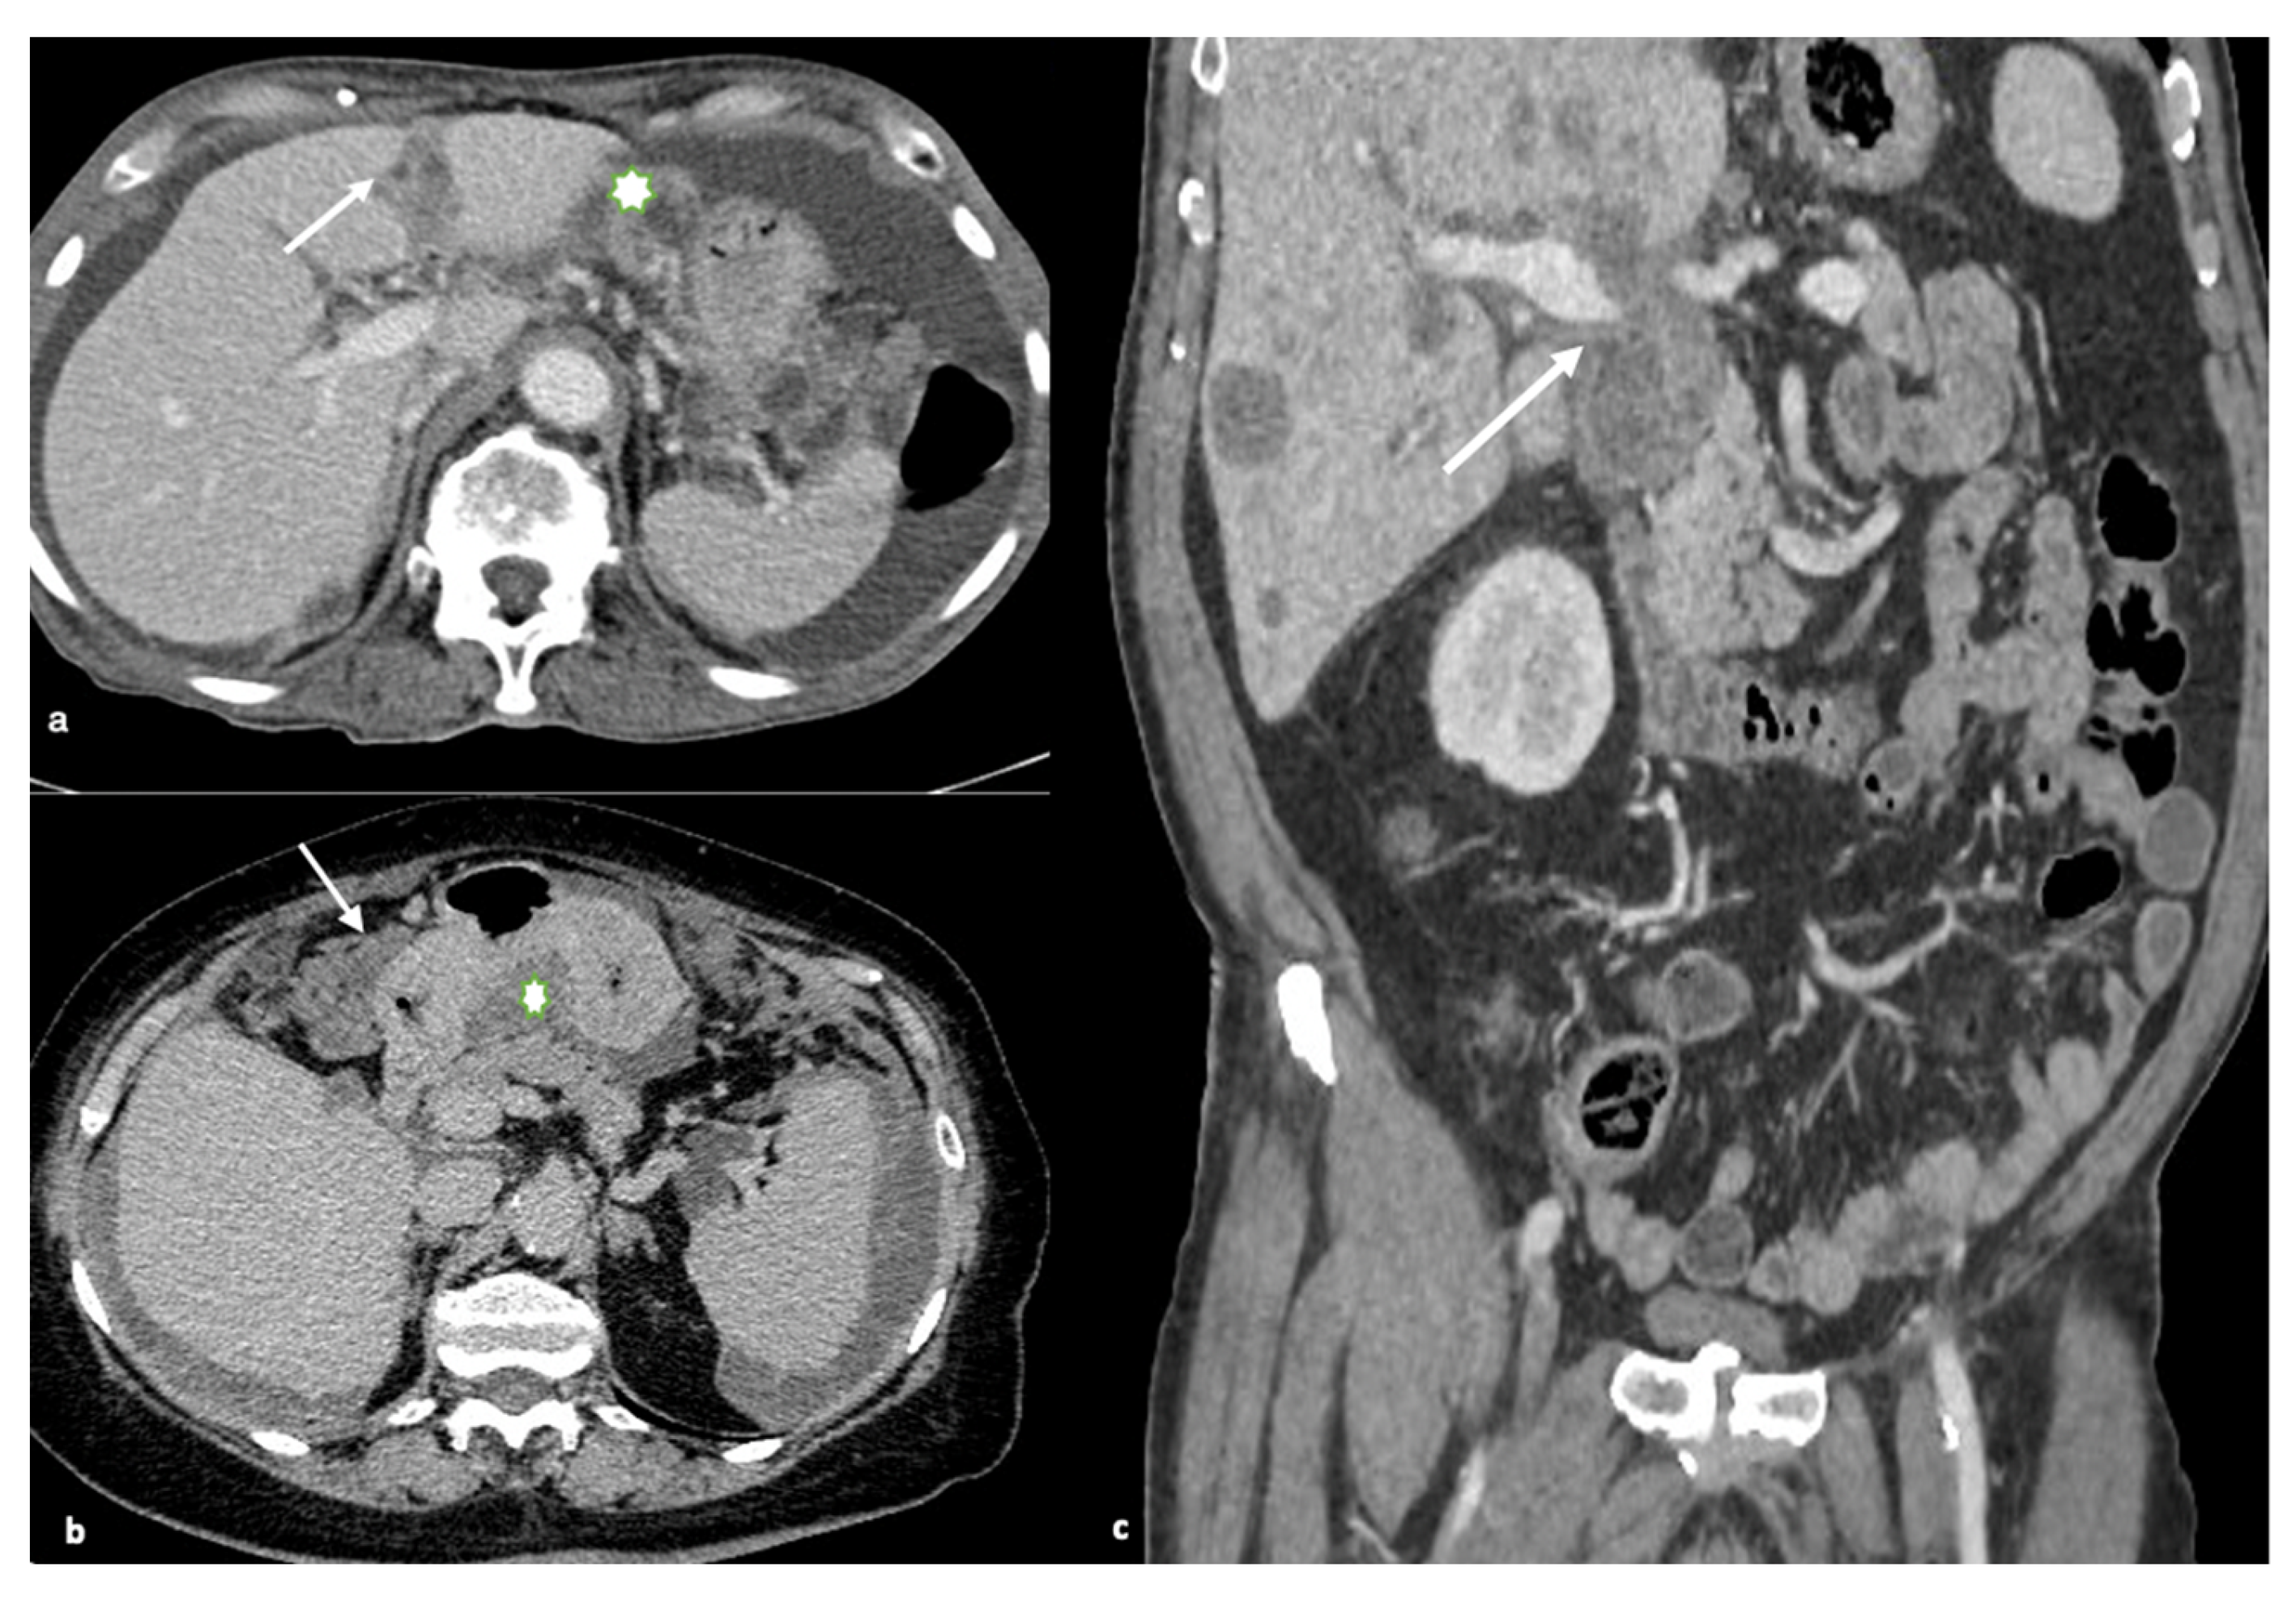

The falciform ligament, gallbladder fossa, and periportal space must all be closely examined. Carcinomatous lesions in these areas, particularly those larger than 2 cm, are often predictive of non-optimal debulking. High-grade nodules with sclerotic characteristics could limit or even obstruct the normal hepatic ducts. Tumors with large volumes in the gastrohepatic ligament can also cover the left gastric artery. Enhancing soft tissue that extends along the portal veins is direct evidence of tumor spread along this peritoneal pathway, as is the presence of ill-defined infiltration of the gallbladder fossa (Figure 4).

The spread of disease anterior and posterior to the stomach’s antrum can cause gastric outlet obstruction.

Figure 4. Gastro-hepatic or hepatoduodenal ligaments and gastric outlet obstruction. (a) Axial contrast-enhanced image shows multiple peritoneal deposits involving the falciform ligament (arrow) and gastro-hepatic ligament (asterisk), (b) Axial contrast-enhanced images show the spread of disease anterior (arrow) and posterior to the stomach (in the lesser sac; asterisk). This latter condition may result in gastric outlet obstruction, (c) Coronal contrast-enhanced image demonstrates a large, bulky mass in the porta hepatis and hepatoduodenal ligament with mass effect on the portal vein (arrow).